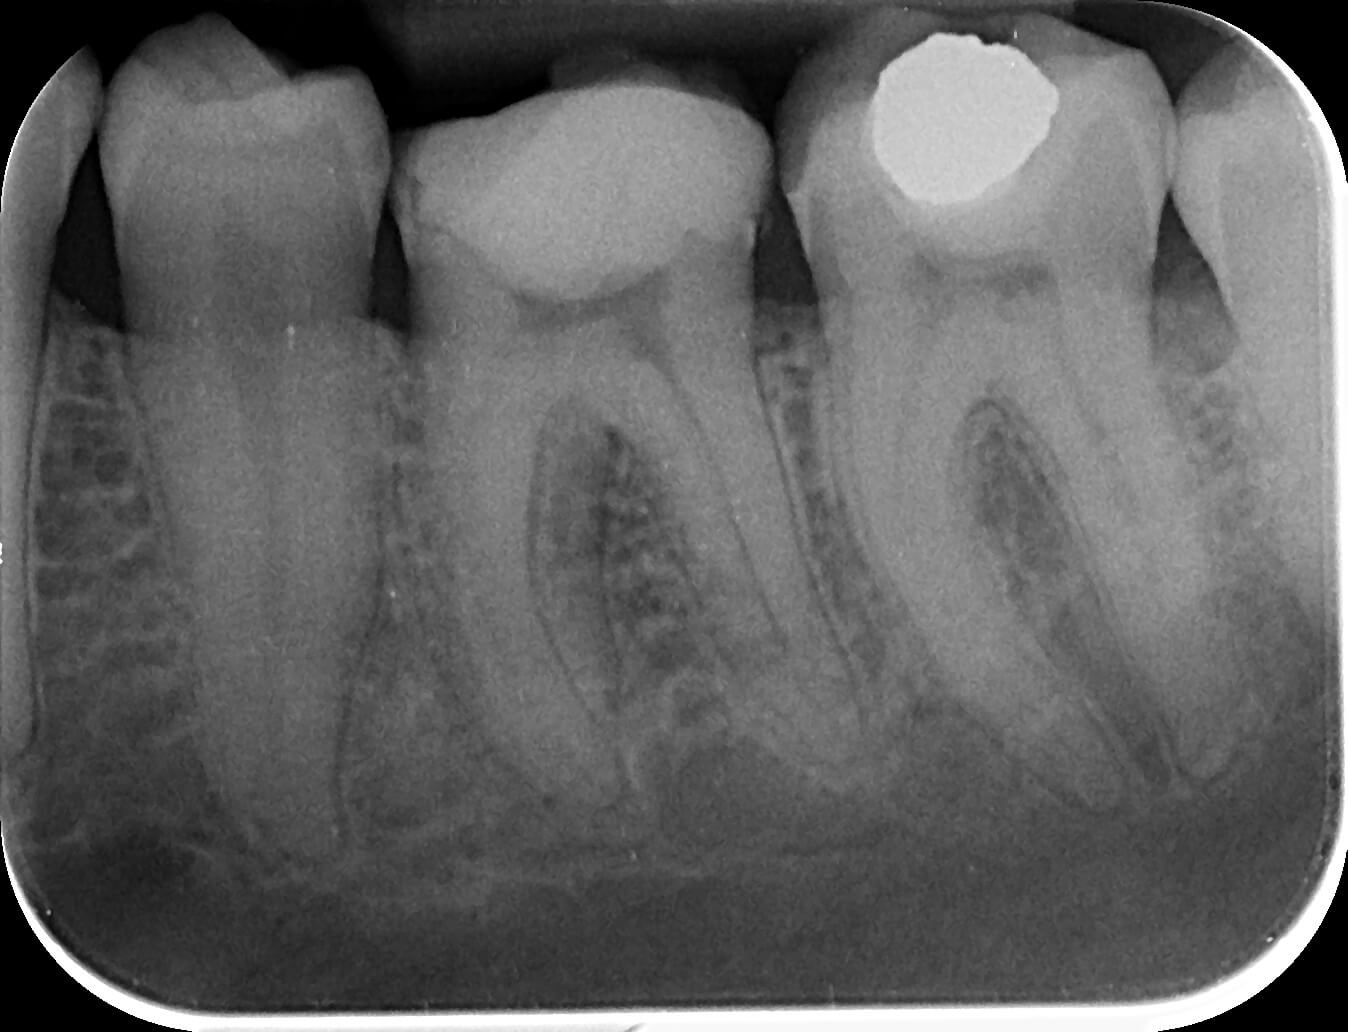

Canale înguste

Înainte și după

Canale largi